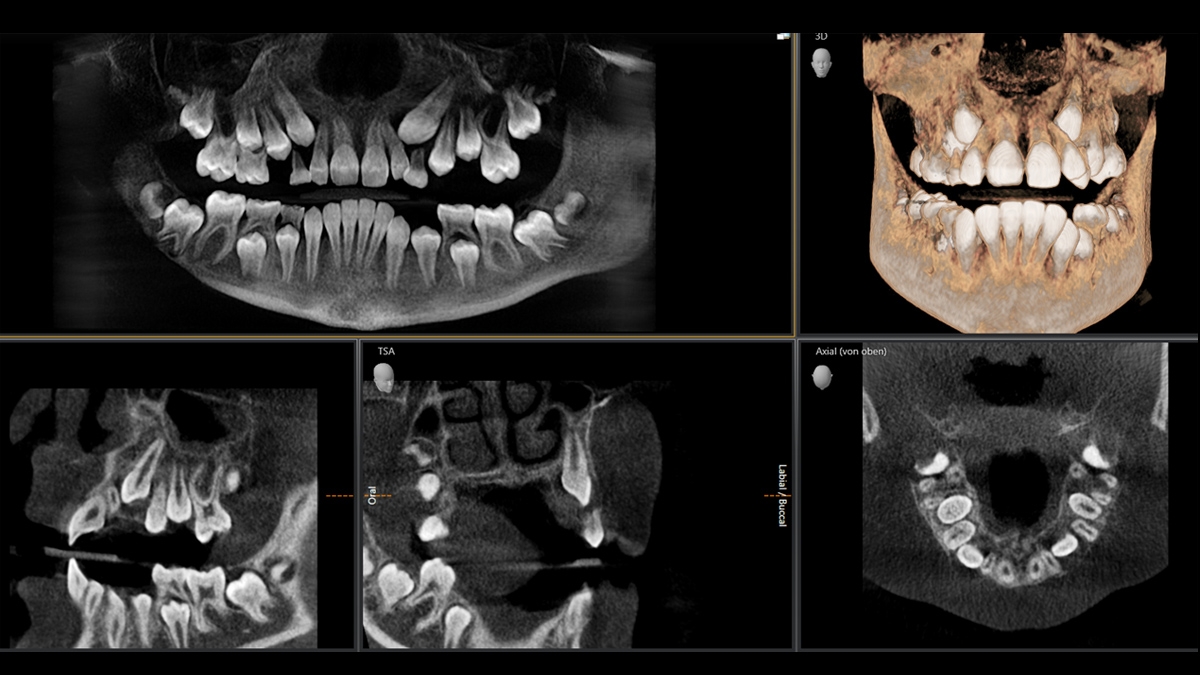

3D示例图

智能低剂量

由于采用专用滤波器优化了低剂量模式,有可能在大幅降低剂量的情况下实现致密结构(如骨骼)成像。因此,在许多临床情况中,智能低剂量是一项充满吸引力且高效的选择。无论是在口腔正畸还是牙齿种植——借助登士柏西诺德解决方案,您将为每一个病例找到更佳调整方案。

3D低剂量适用于各种临床情况。

与传统的低剂量方法相比,登士柏西诺德智能低剂量方法不仅降低了电流值(mA),而且还应用了专用的铜过滤器。尽管剂量低,但致密结构(例如骨)的可见性增强。

使用登士柏西诺德成像解决方案,您只需点击一下,就可以确保在2D X射线的剂量范围内获得3D信息。

3D低剂量适应症实例